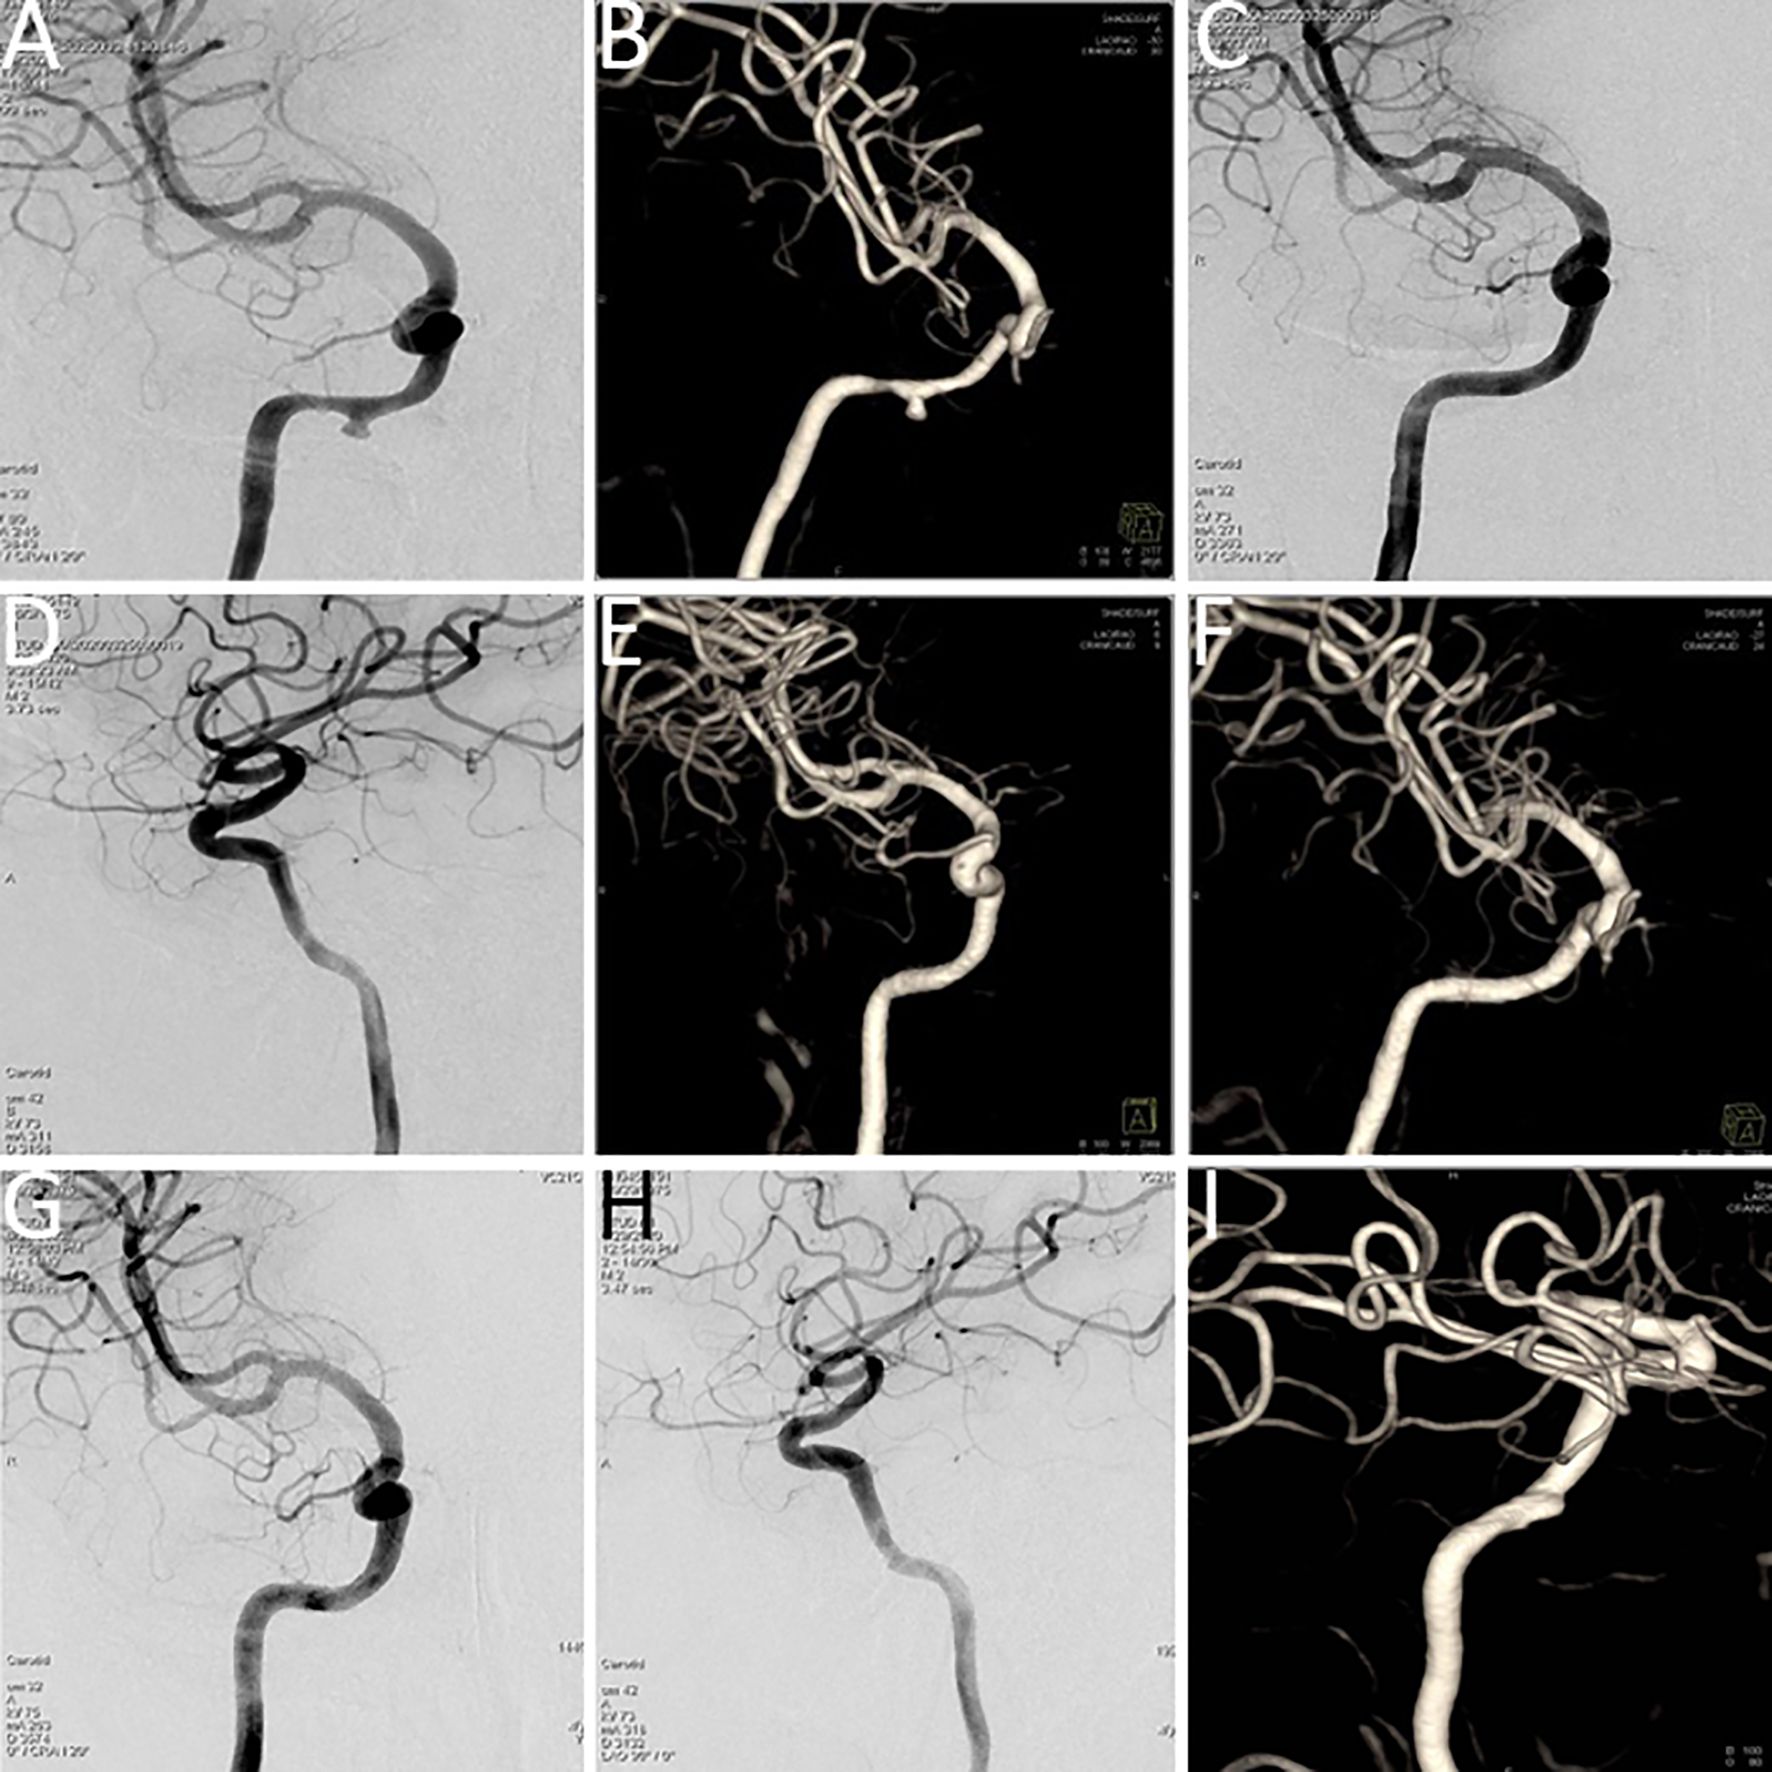

Considering the patient’s concurrent systemic conditions, arterial interventional infusion chemotherapy was selected. The chemotherapeutic agents, docetaxel and carboplatin, were diluted and administered via intra-arterial infusion (20 mL) through branches of the ascending pharyngeal artery or internal maxillary artery (refer to Figure 5).

Figure 5

Arterial interventional chemotherapy for nasopharyngeal carcinoma targeting the ascending pharyngeal artery or internal maxillary artery branches, with intra-arterial infusion of docetaxel and carboplatin (20 mL). (A) ascending pharyngeal artery; (B) internal maxillary artery branches.